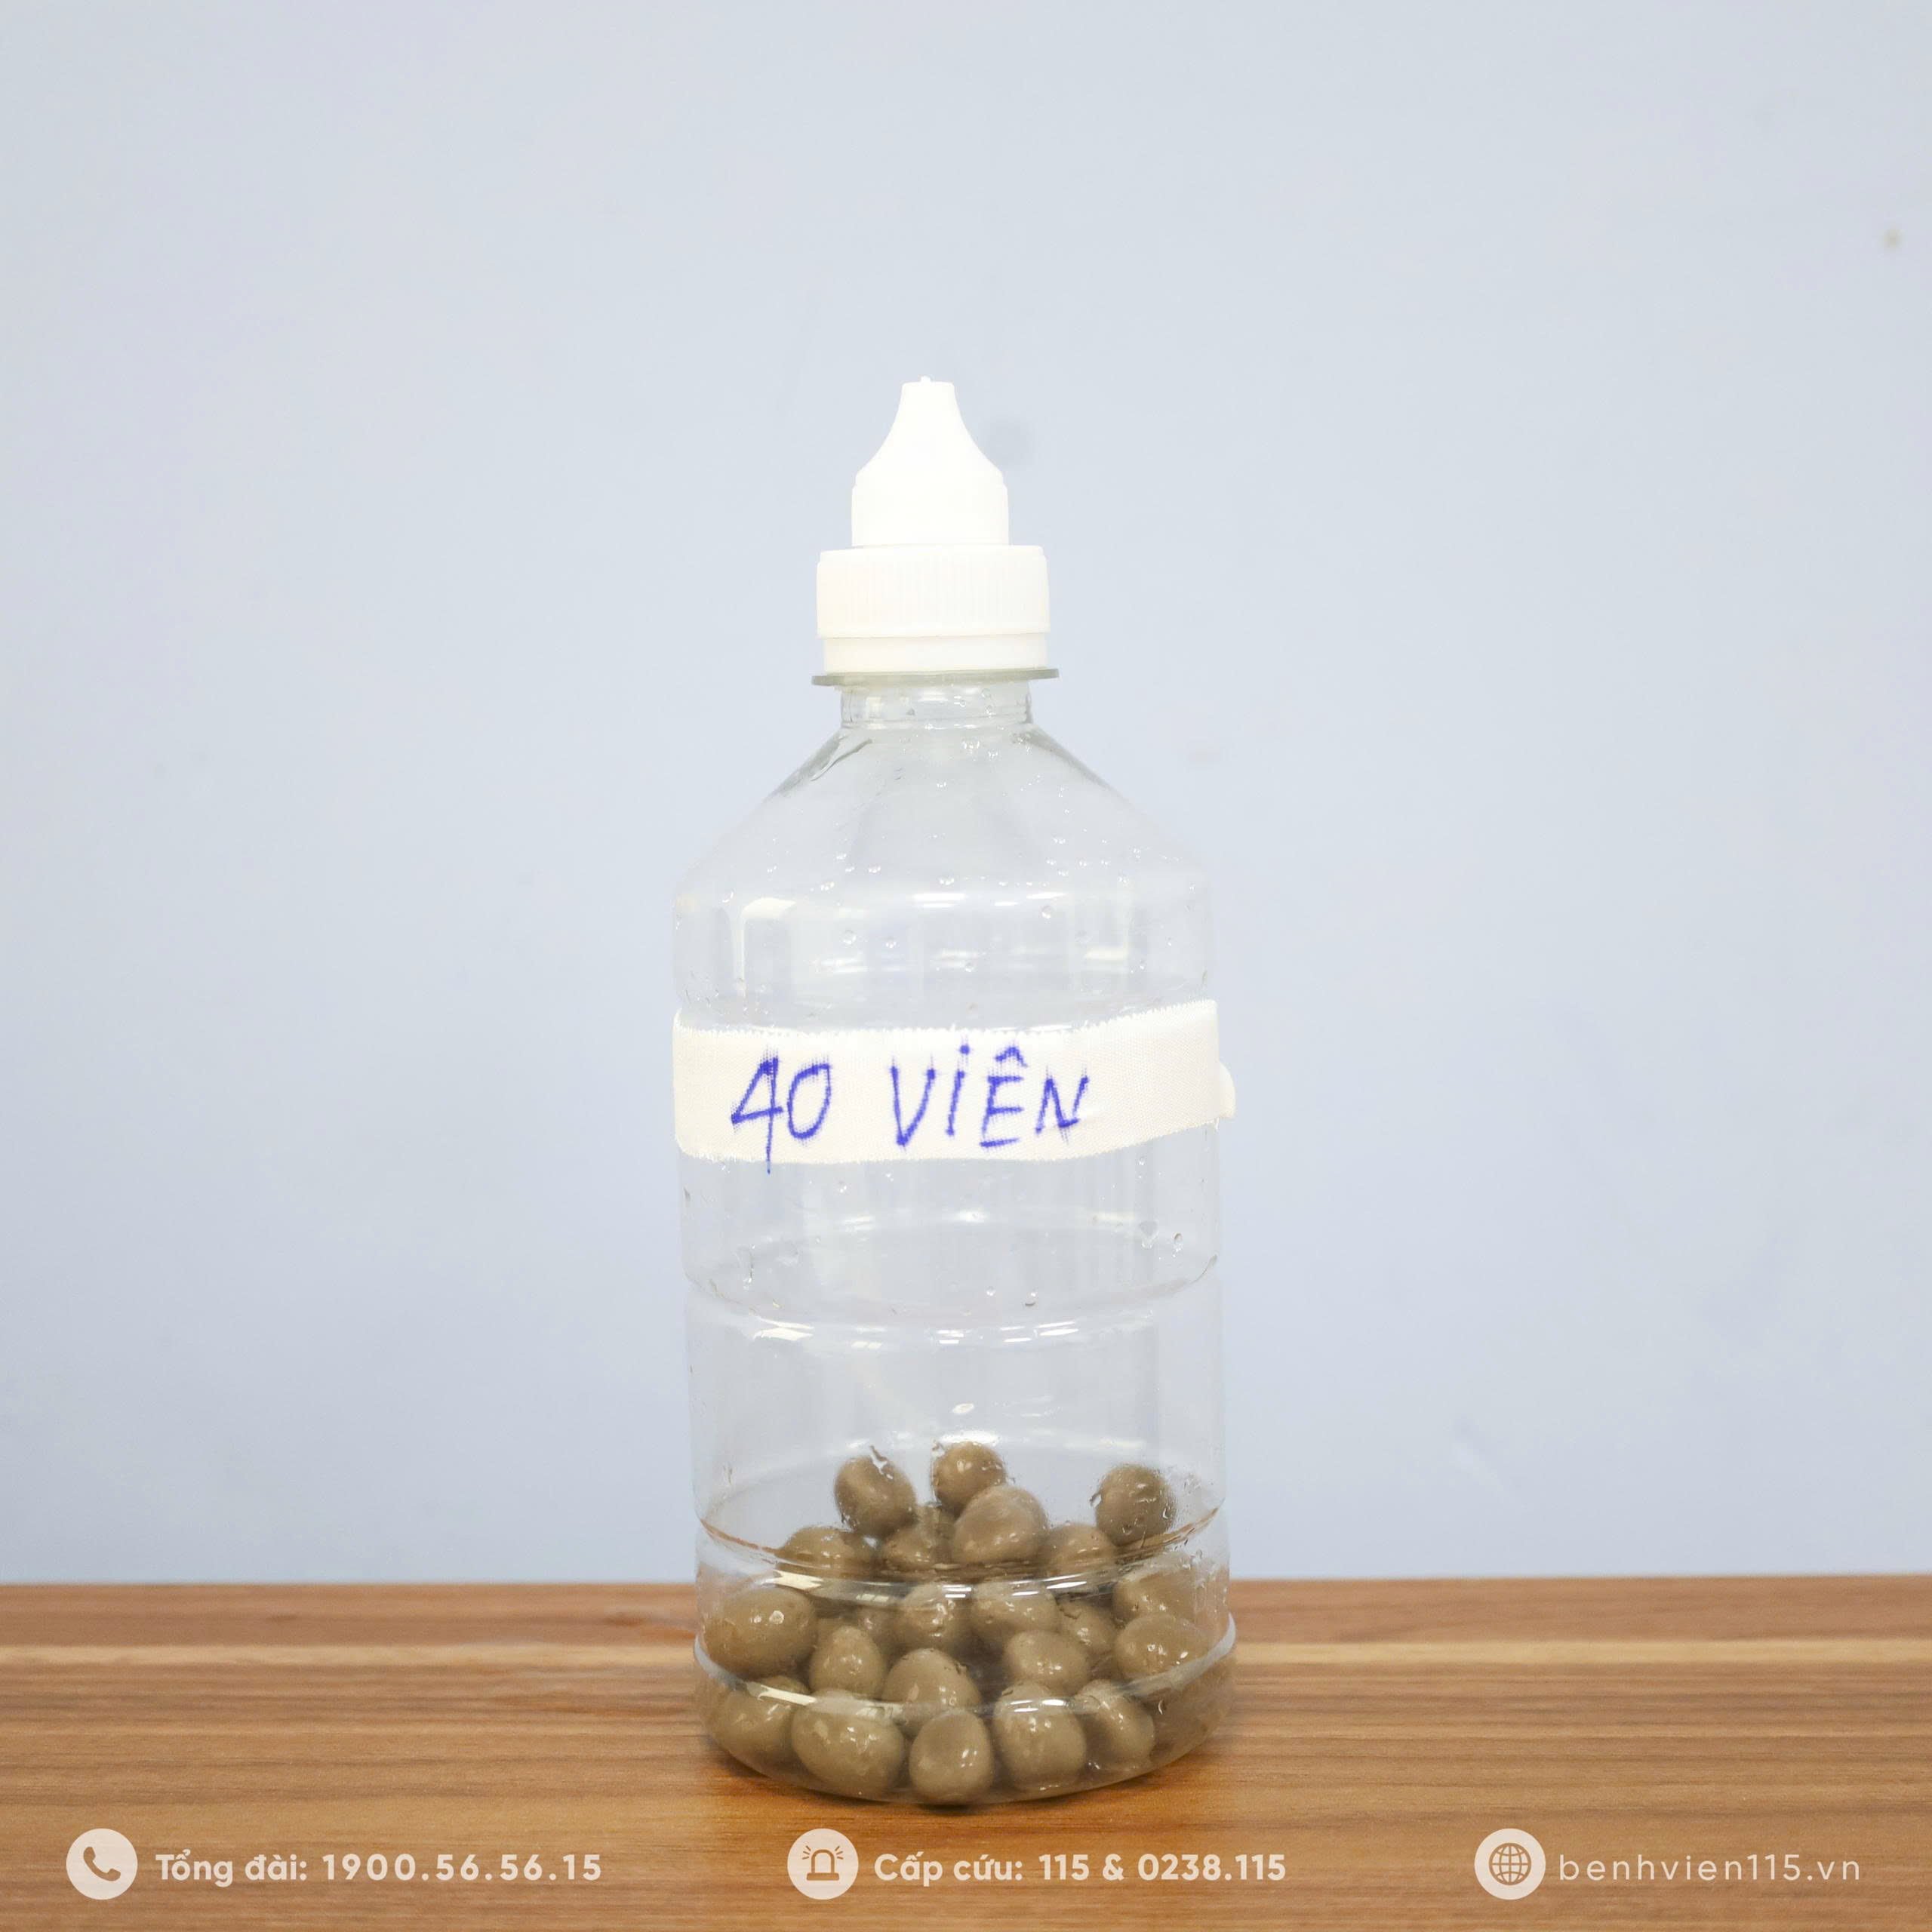

40 viên là số lượng sỏi mà ekip phẫu thuật tại Bệnh viện 115 Nghệ An đã lấy ra từ bàng quang của ông T.A.T (79 tuổi – Nghệ An).

40 viên là số lượng sỏi mà ekip phẫu thuật tại Bệnh viện 115 Nghệ An đã lấy ra từ bàng quang của ông T.A.T (79 tuổi – Nghệ An).